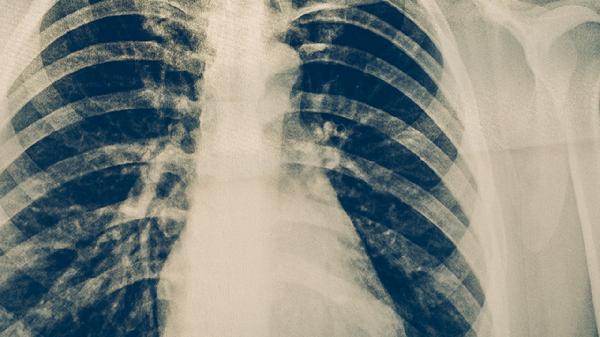

胸部X線檢查能發(fā)現(xiàn)肺部浸潤影、空洞等典型結(jié)核病灶,適用于初步篩查。胸部CT檢查分辨率更高,可清晰顯示微小病灶和縱隔淋巴結(jié)腫大,對早期不典型肺結(jié)核的診斷價值更大。影像學(xué)表現(xiàn)需結(jié)合臨床癥狀和其他檢查綜合判斷。